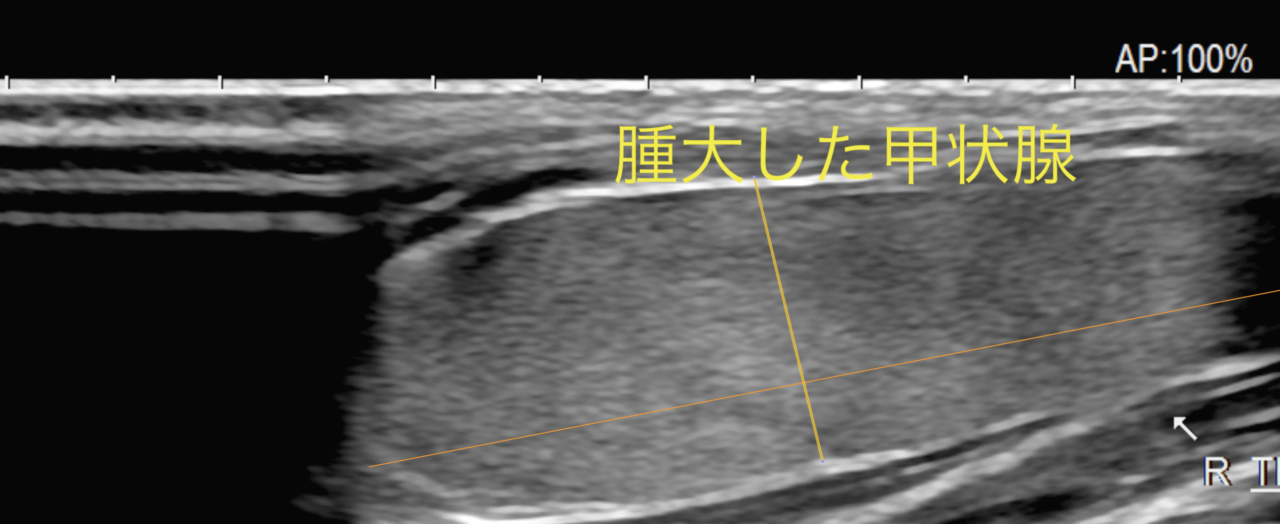

高齢の猫によく見られる病気に甲状腺機能亢進症があります。診断には注意深い頸部の触診(サイロイドスリップ)、血液検査でT4の上昇があるか?などで診断を行います。治療は日本では内科療法と外科療法が行われています。甲状腺機能亢進症の猫ちゃんに被膜外甲状腺摘出術を行いました。術後の合併症には低Ca血症、ホルネル症候群、喉頭麻痺、声の変化、甲状腺機能低下症、慢性腎機能障害の表面化などが挙げられます。通常、心筋肥大、頻脈、高血圧などが伴っている事があるので手術の前までに治療しておく必要があります。両側摘出した場合は定期的にCaやT4、腎機能のモニタリングが必要です。高齢ながら頑張ってくれました。高齢の猫ちゃんはのどの辺りに触れるしこりがないか?時々、触っておきましょう。まれに甲状腺癌が隠れていることがあるので摘出した臓器は病理検査で調べておきます。